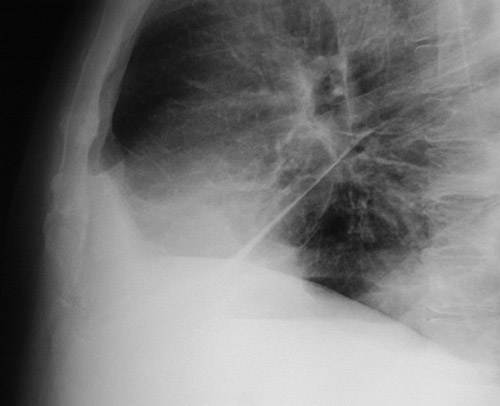

| The magnified view of the chest radiograph in lateral view above demonstrates fluid in the major fissure in a patient with left heart failure. The increased fluid in lymphatics around bronchi creates a circular outline to the bronchi as seen in cross section. The entire lateral view is seen below. |